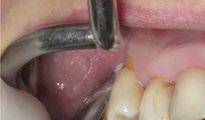

Para ilustrar el proceso, presentamos el caso de una mujer joven diagnosticada de carcinoma adenoide quístico en la región posterior del hemipaladar izquierdo (Figuras 1 y 2). El procedimiento quirúrgico realizado fue una

maxilectomía parcial que incluyó las piezas 24-26 y desde el reborde alveolar hasta la base del cráneo (Figuras 3 y 4). En este caso, la órbita y el globo ocular pudieron ser preservados. La reconstrucción inmediata se realizó mediante un colgajo de músculo temporal homolateral (Figura 5) y el defecto de la fosa temporal fue cubierto mediante una malla de titanio. Posteriormente, la paciente recibió radioterapia (Figuras 6 y 7). 2 años más tarde se diseñó un IS con anclaje en el arbotante nasomaxilar, zona subnasal izquierda

Figura 3. Maxilectomía parcial.

Figura 4. Defecto maxilar tras resección del tumor.